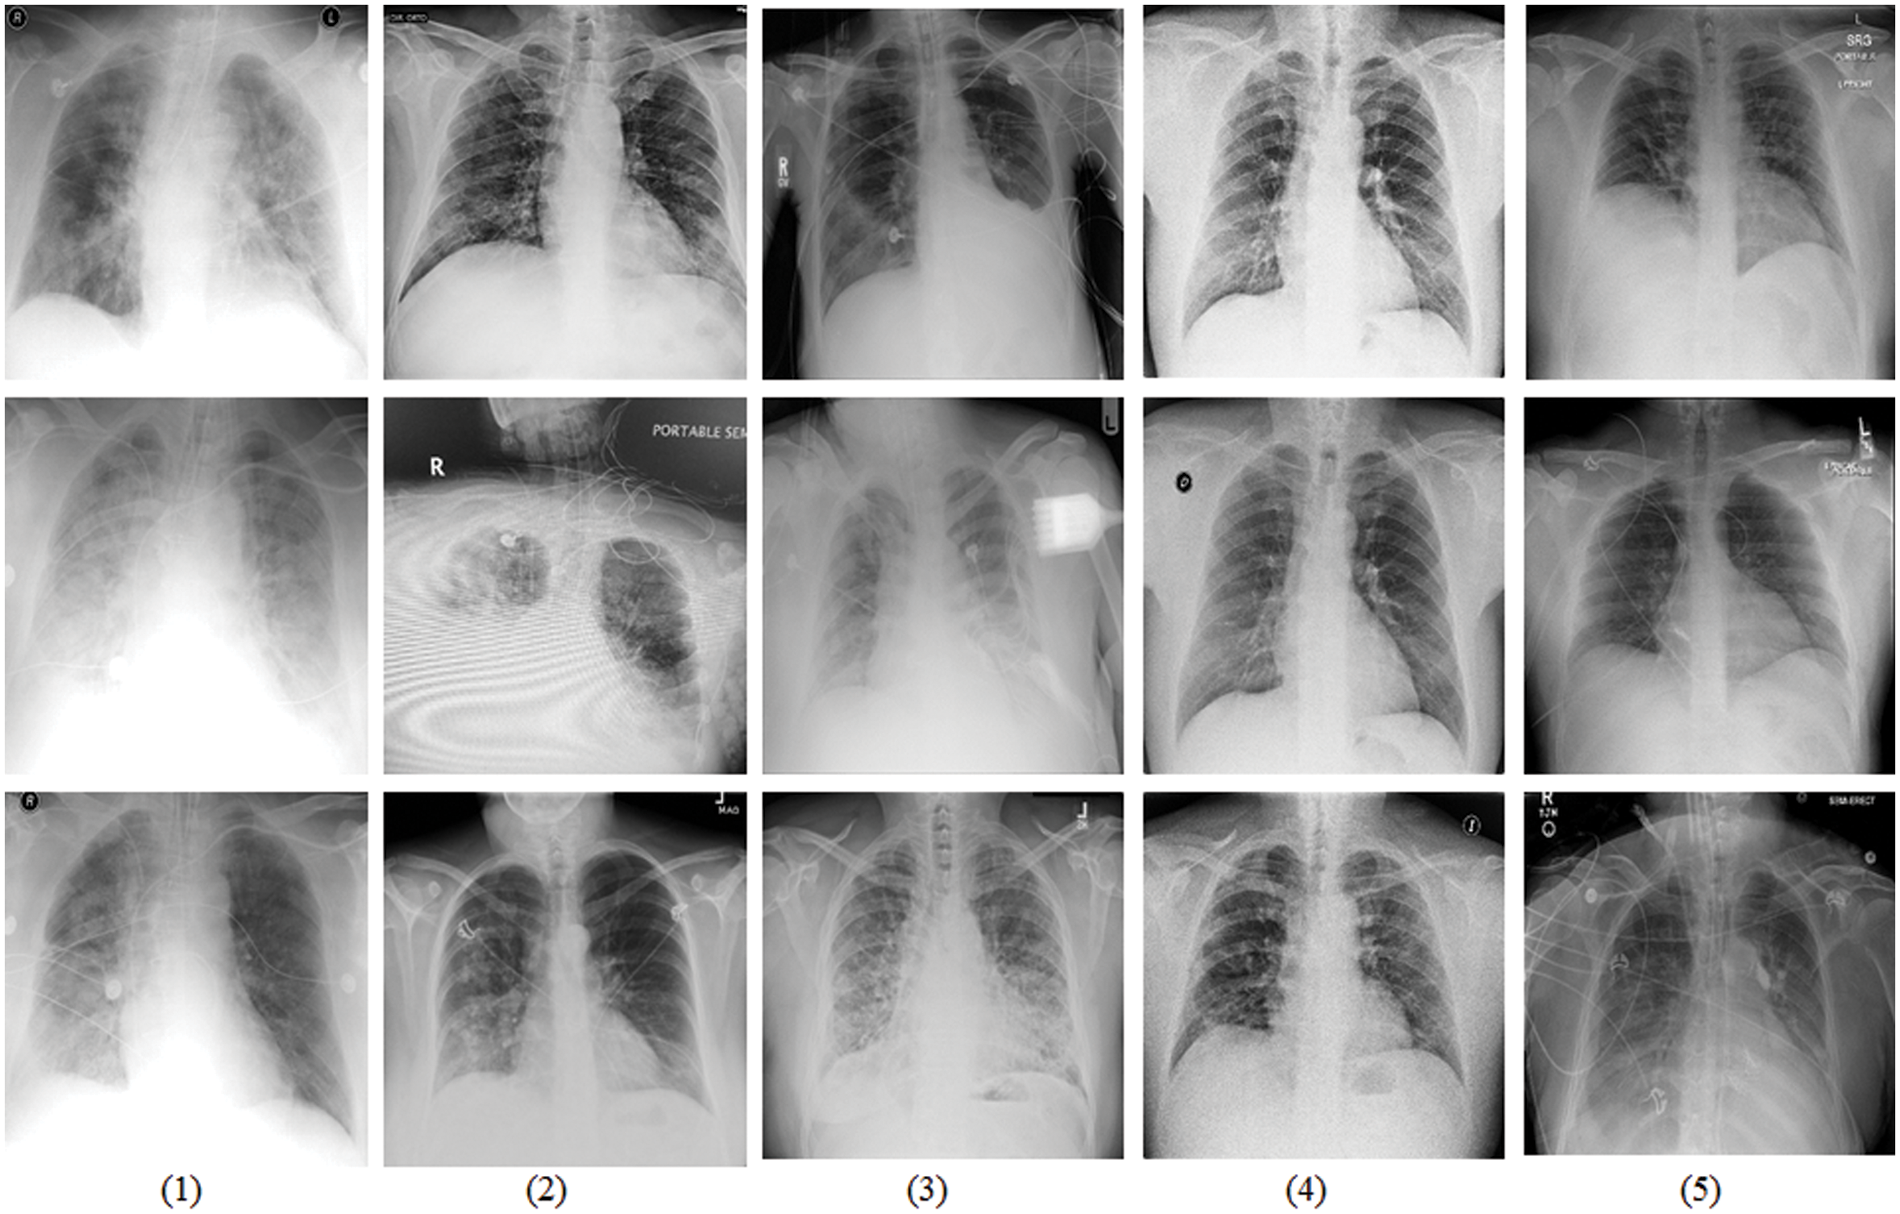

The COVIDx dataset is an open source benchmark dataset and generated by the images that are from different data repositories, as shown in Fig. 5. The COVIDx dataset includes 13,975 CXR images collected from 13,870 patient cases. Especially, The COVIDx dataset comprises a large number of COVID-19 positive patient cases.

Figure 5: Sample data display from the COVIDx dataset that is tailed from different data repositories [42]. (1) COVID-19 Images collected by [43], (2) COVID-19 Chest X-Ray images from the link [44], (3) The images are from RSNA Pneumonia Detection challenge dataset [45], (4) Providing by ActualMed COVID-19 CXR Dataset [46], and (5) The images are from COVID-19 radiography repositories [47]

All the images of the COVIDx dataset are classified three classifications: normal, non-COVID-19 pneumonia, and COVID-19 viral infection. In detailed, Non-COVID-19 pneumonia patient cases are mainly from the COVID-19 Image Data Collection. The COVID-19 pneumonia cases are from five different data repositories. There are many advantages to use CXR images to study the COVID-19 pneumonia to assist diagnosis and treatment: